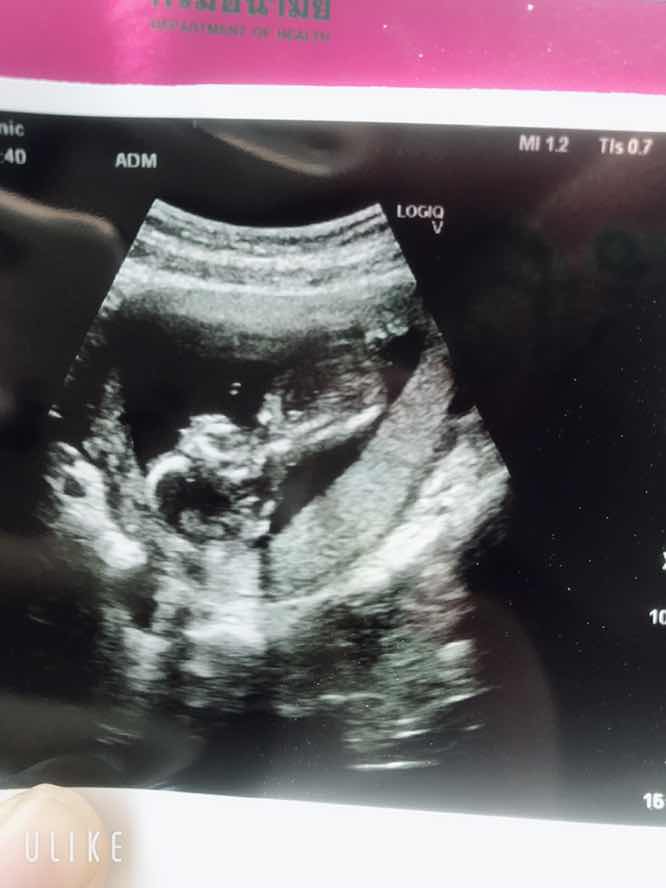

กำลังตั้งครรภ์